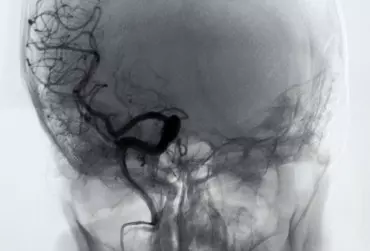

Interfejsy mózg–komputer oparte na P300 w neurorehabilitacji

Postęp nauk medycznych oraz techniki medycznej powoduje ciągłe doskonalenie metod leczenia i rehabilitacji, niosąc ratunek i pomoc w cierpieniu pacjentom w coraz cięższych stanach, takich jak poważne deficyty neurologiczne powstałe wskutek uszkodzeń traumatycznych (w tym jako rezultaty wypadków komunikacyjnych), udarów, uszkodzeń rdzenia kręgowego, schorzeń neurodegeneracyjnych, chorób metabolicznych czy zatruć.